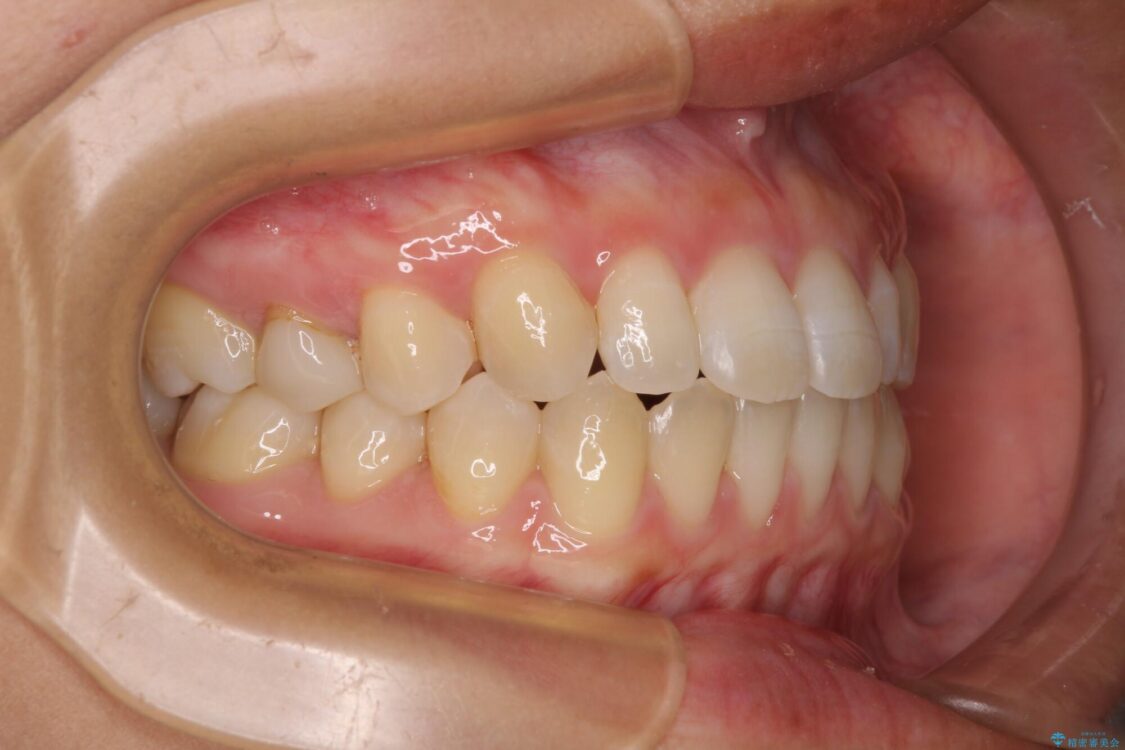

治療途中

• 隙間だらけの歯列 インビザラインで改善 治療途中画像